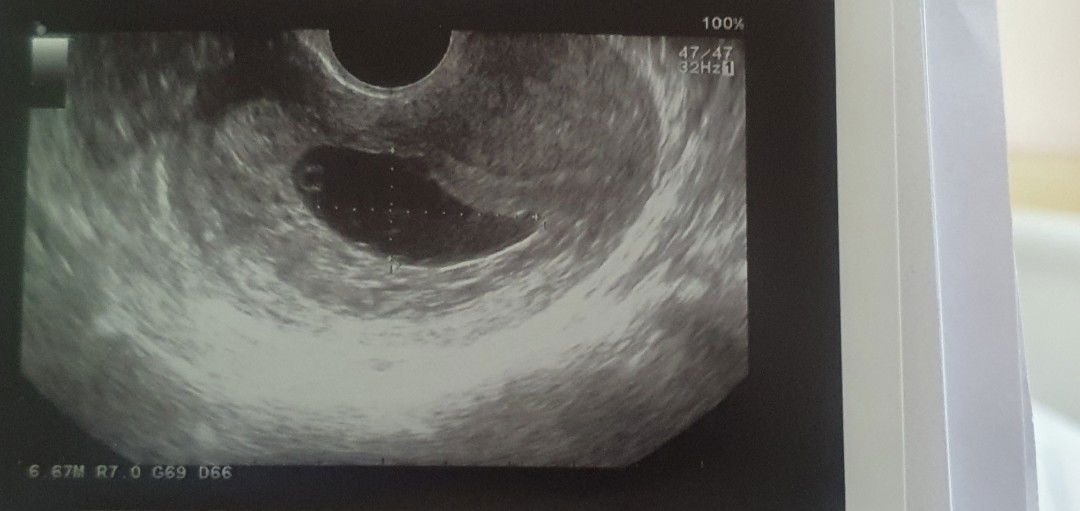

ท้องลม

เราอายุ35ปี ท้องแรก มาฝากครรภ์กับรพ. ซาวน์ครั้งแรกตอน6w หมอแจ้งว่าท้องปกติ ท้องในมดลูก ซึ่งวันนั้นก้อไม่ได้บอกนะว่าเด็กมีหัวใจเต้นรึไม่ จนเรา12w มาหาหมอเผื่อเจาะเลือดตรวจโคโมโซม หมอถามว่า ตัวเด้กอายุเท่ารัยเราก้อไม่รู้ หมอจึงให้ซาวน์มาพบว่า ไม่มีเด้กมีแต่ถุงน้ำคร่ำที่ขยายขึ้น และจุดไข่แดง (ก่อนหน้านี้อาการเราเหมืนคนท้องปกติ ไม่เคยมีเลือดออก รึอาการปวดท้องใดๆเลย รวมทั้งเราบำรุง กินโฟเลทก่อนท้องเปนปี จนปัจจุบัน)เคยอ่านเลยท้องลม แต่ไม่คิดว่าจะเกิดกับตัวเอง ตอนนี้เราได้ขูดมดลูกเปนที่เรียบร้อย อยากรุ้ว่ามีคนที่ขูดมดลูกแล้วไม่มีลูกอีกเลยไหม อยากมีลูกมากกัวเค้าจะไม่มาอีก ปล.ไปซาวน์ที่คลินิกอีกรอบเพื่อให้ชัวร์ หมอบอกว่าจิงๆควรจะรุ้ตั้งแต่ซาวน์ครั้งแรกเมื่อ 6w รึรพ.ไม่ดี(รพ.รัฐแถวเสาวรีย์)